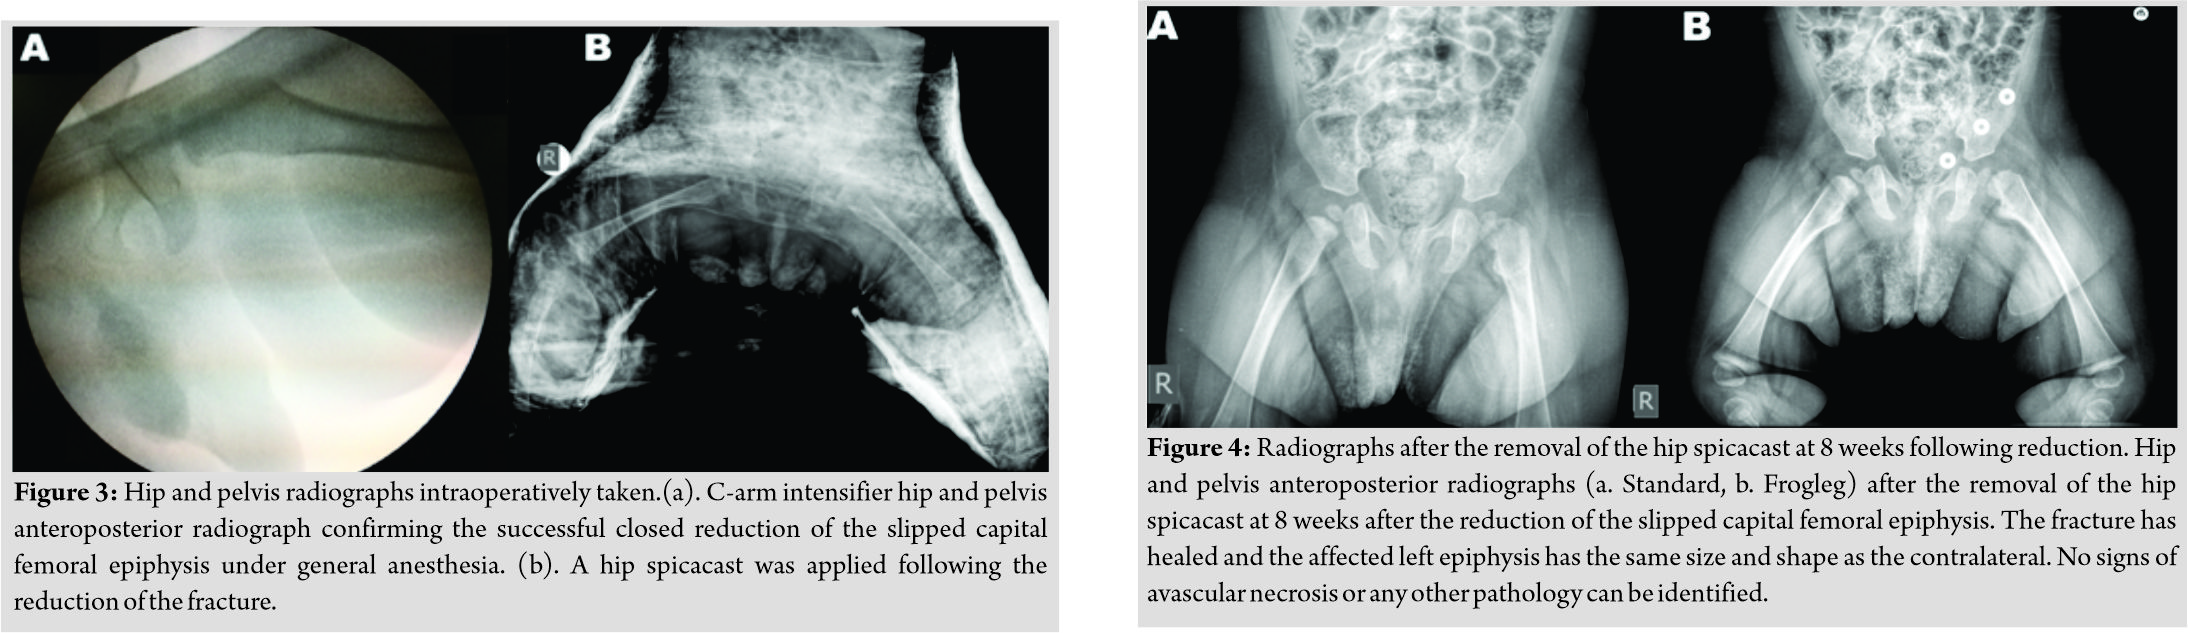

Physical examination revealed an otherwise healthy infant, with normal weight, height, and cranial perimeter for his age. The patient’s lower left limb appeared to be in pseudoparalysis;it remained in external rotation and every attempt to passively move it was painful. Routine blood test results (including inflammatory markers) were all within normal range. However, a radiograph revealed the existence of SCFE in the left hip (Fig. 1). A skin traction was put in place for analgesia and as a means to initiate– if possible– reduction of the fracture and the patient next underwent amagnetic resonance imaging (MRI)scan (Fig. 2), which confirmed the SCFE and excluded any other pathology.

The patient was followed up at our outpatients’ clinic every week for the 1stmonth and then every 15 days for another month. The spicacast was removed at 8 weeks (Fig. 4). Physical examination at this stage revealed a painless hip with a full range of motion. The patient’s physiotherapy and passive kinesiotherapy routine resumed at 6-month post-reduction. Despite the fact that he was not able to walk (and remained non-ambulatory on his latest follow-up visit) suffering from severe psychomotor dysfunction in the context of epileptic encephalopathy, painless hip range of motion was retained during all follow-up visits throughout the next 22 months. Consecutive follow-up radiographs obtained during the follow-up period, revealed good remodeling of the proximal femur and a femoral head with spherical contour and with no signs of avascular necrosis or chondrolysis (Fig. 5). An MRI scan at 2 years post-reduction showed normal shape and size of the affected femoral head, with no signs of physeal arrest and/or avascular necrosis (Fig. 6). Nevertheless, the child is under a tight follow-up schedule and it will remain under close observation until he has reached skeletal maturity.